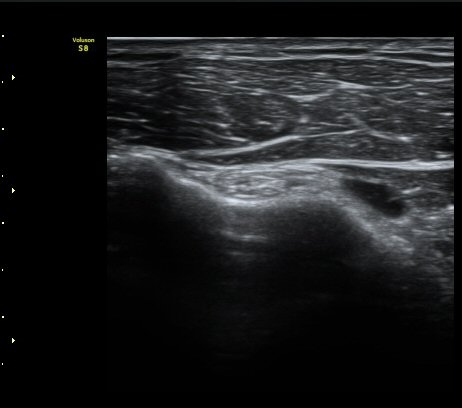

±Ø»ó°Ç Á¾´Ü¸é°Ë»ç»ó ±Ø»ó°Ç ³»Ãø ºÎÂøºÎ¿¡¼­ °Ç¿¬°á¼º ¼Ò½ÇÀÌ °üÂûµÈ´Ù(±×¸² 7, 8).

±Ø»ó°Ç Á¾´Ü¸é°Ë»ç»ó ±Ø»ó°Ç ¼Ò½Ç¿¡ ÀÇÇÑ È¸Àü±Ù°³ °á¼ÕÀÌ °üÂûµÈ´Ù(±×¸² 9, 10).